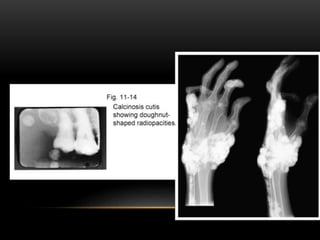

OSTEOMA CUTIS

• These are sites of normal bone formation in abnormal locations. It

is a rare soft tissue calcification in the skin.

• It may develop secondary to acne of long duration. In a scar or

chronic inflammatory dermatosis.

• Histologically these are seen as areas of dense viable bone in the

dermis or subcutaneous tissue.

• They are occasionally found in diffuse scleroderma, replacing the

altered collagen in the dermis and subcutaneous septa.

RADIOGRAPHIC FEATURES

• An intraoral film placed between the cheek and the alveolar bone

gives accurate localization.

• A posteroanterior skull view with the cheek blown outward using a

soft tissue technique of 60 kVp helps localize osteomas of the

skin.

• If present in the cheek or lip region the shadow may be

superimposed over a tooth root or alveolar process, giving the

appearance of dense bone.

• The osteoma cutis appears as smoothly outlined, radiopaque,

washer-shaped images.

• •The single or multiple radiopacities of various sizes.

• • It appears as a homogeneous radiopacity with a radiolucent

center that represents normal fatty marrow, giving the lesion a

dough-nut appearance radiographically.

• • Trabeculae usually develop in the marrow cavity of the larger

osteomas.

• • Lesions of calcified cystic acne resemble a snowflake radiopacity

which corresponds to the clinical location of the scar.